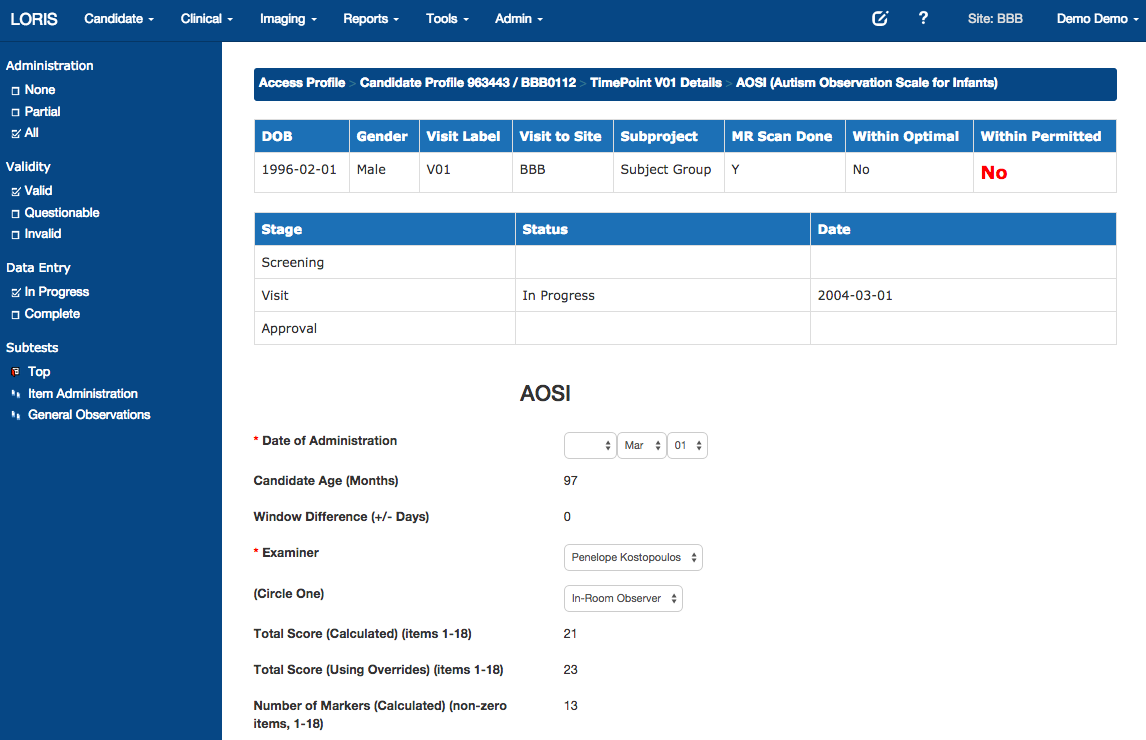

Timepoints

Battery of Measures

Psychometric Data Entry